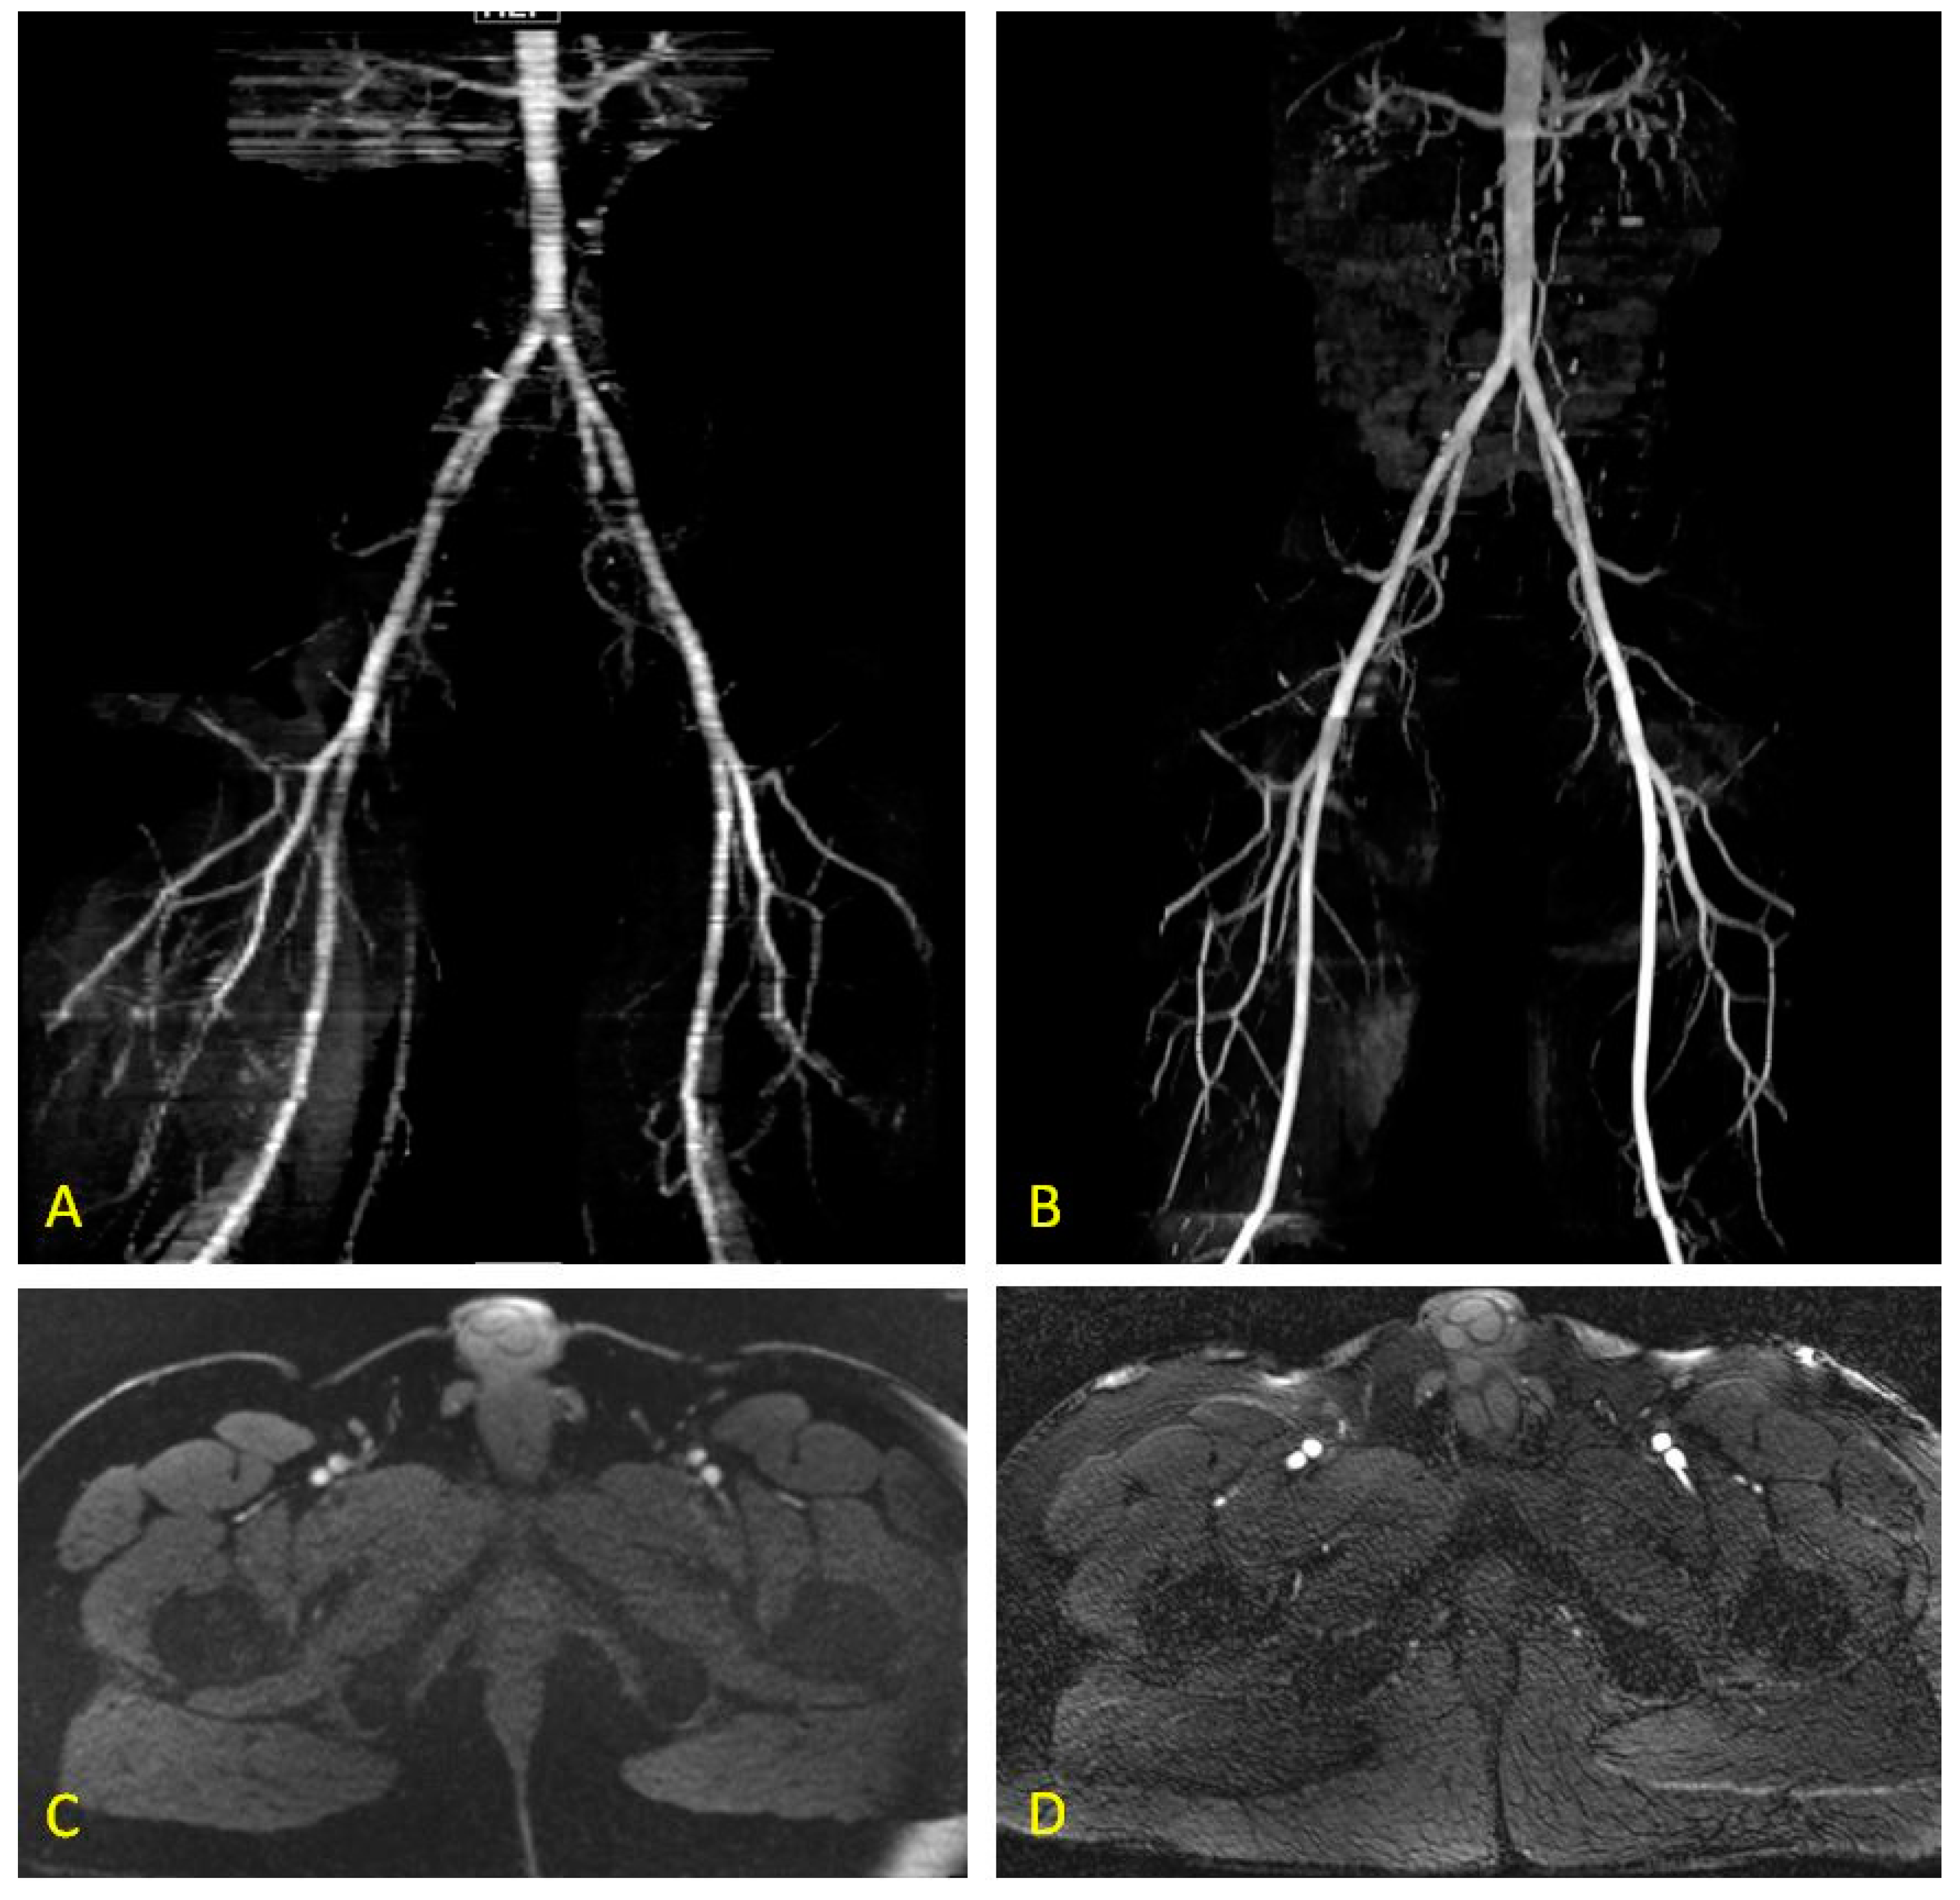

2.5. Quiescent-Interval Single-Shot MRA

3.1. QISS: Technical Considerations and Early Feasibility studies